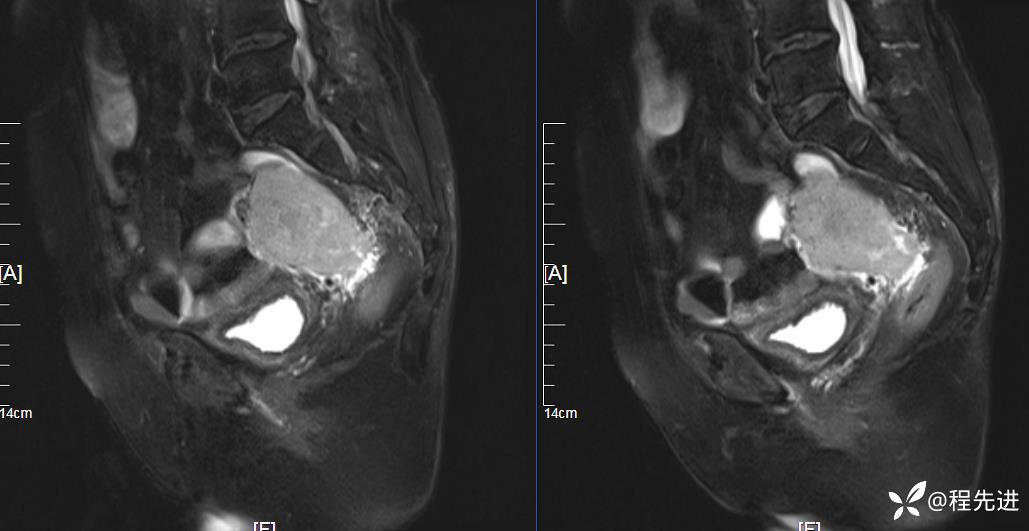

T2压脂: